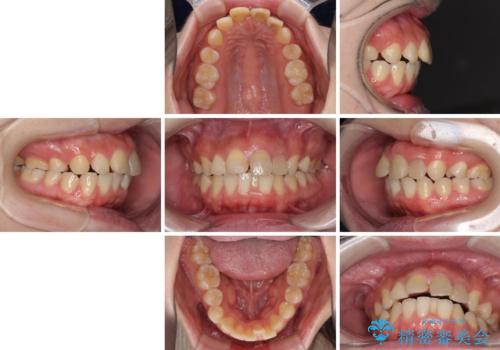

抜歯矯正の後戻り インビザラインによるオープンバイトの再矯正

- 以前矯正治療をされていましたが、後戻りが起きたことを気にして来院された患者様です。

上下前歯のオープンバイトを改善するため、インビザラインにて治療を行うこととしました。